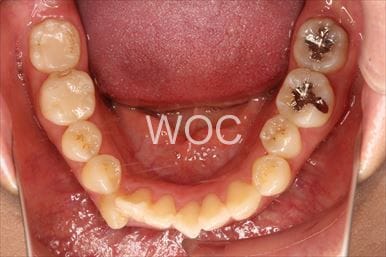

出っ歯エッジワイズ装置

特に装置の希望はなかったので、エッジワイズ装置を選択。

歯の移動量が大きいので歯根吸収の可能性がありましたが、目立った吸収は見られませんでした。-

- 年齢:17歳女性

- 主訴:出っ歯、前歯のガタガタが気になる

- 基本矯正料金:78万円

- 治療期間:1年2ヶ月

- 抜歯部位:上顎両側第一小臼歯